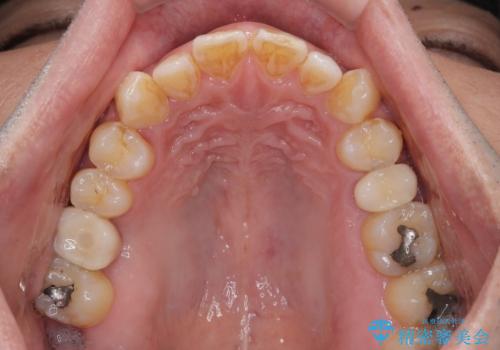

インプラント処置は、抜歯即時埋入を行い、十分な安定性が確認できたため、当日仮歯を装着しました。

インプラントが生着するのを待っている間に反対側の根管治療を行い、左右同時に補綴治療を行いました。

補綴治療後3ヶ月での経過は良好で、引き続き経過観察を行っていきます。